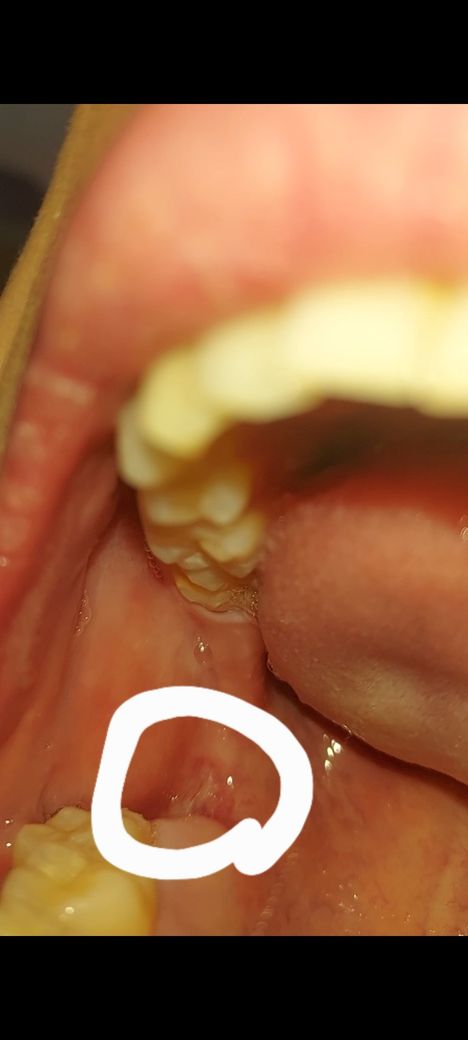

2주전에 생겼던 물집같은게 아직 혀로 조금 잡히네요..그 부위가 아프진않아요 밑에 동그라미친 부분 구강암인지 너무 걱정되네요..도와주세요 ㅠㅠ 병원 가봐야죌까요?

사진으로 보기에 단순히 잇몸에 상처가 난 것으로 보입니다.

구강암은 아닙니다. 1-2주 더 기다려도 없어지지 않으면 치과 검진 권합니다.

현재 보이는 부분으로는 정확한 판단이 어렵지만 구강암의 일반적인 모양은 아닙니다. 구내염이나 잇몸 상처에 더 가까워 보입니다. 다만 대부분 구내염 및 잇몸 상처는 2주 정도 지나면 서서히 회복되나 시간이 지나도 회복되지 않고 그 범위가 커지는 것 같다면 반드시 치과 방문 후 해당 부위에 대한 정확한 평가가 필요합니다.